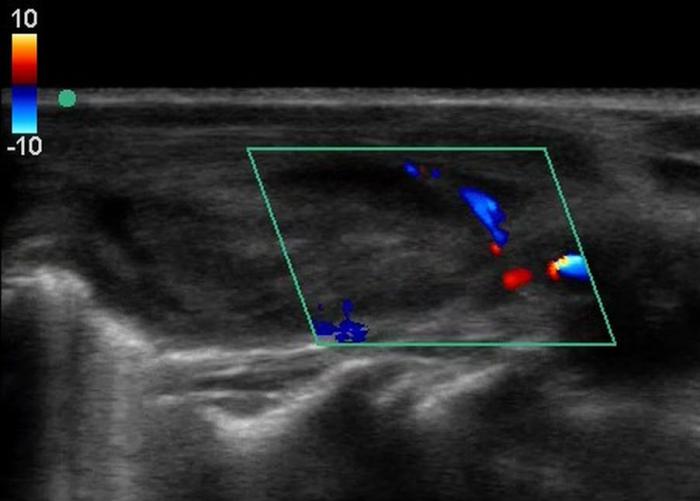

El Doppler color y espectral es especialmente útil para valorar la vascularización glandular. Un patrón de flujo periférico leve y simétrico es considerado normal. El aumento en la intensidad, desorganización o presencia de flujo central puede sugerir procesos funcionales como el hipertiroidismo o lesiones neoplásicas9.

En perros con hipotiroidismo adquirido, los hallazgos ecográficos típicos incluyen una reducción del volumen glandular, pérdida de la ecogenicidad normal, hipo/hiperecogenicidad difusa, pérdida de la homogeneidad parenquimatosa y, en algunos casos, bordes mal definidos o cápsula engrosada7 (Figuras 6 y 7; Tabla 2). Estas alteraciones reflejan los cambios histopatológicos asociados a procesos inflamatorios crónicos, atrofia glandular o infiltración linfoplasmocítica. El Doppler puede mostrar disminución del flujo o vascularización periférica pobre, aunque este hallazgo no es constante.

Entre las neoplasias más frecuentes se encuentran los carcinomas tiroideos, los cuales suelen presentarse como masas lobuladas, de aspecto invasivo, con pérdida de la cápsula glandular, mineralización distrófica (ver Figura 8), desplazamiento o compresión de estructuras vecinas, y vascularización anómala al Doppler13 (Figura 11A-E).

El uso del Doppler color y espectral ha enriquecido la caracterización vascular de las glándulas tiroideas y paratiroideas. La presencia de flujo central aumentado, vascularización caótica o hipervascularización periférica son signos sugestivos de actividad funcional o de transformación maligna, aunque su interpretación exige experiencia y debe ser contextualizada clínicamente4.